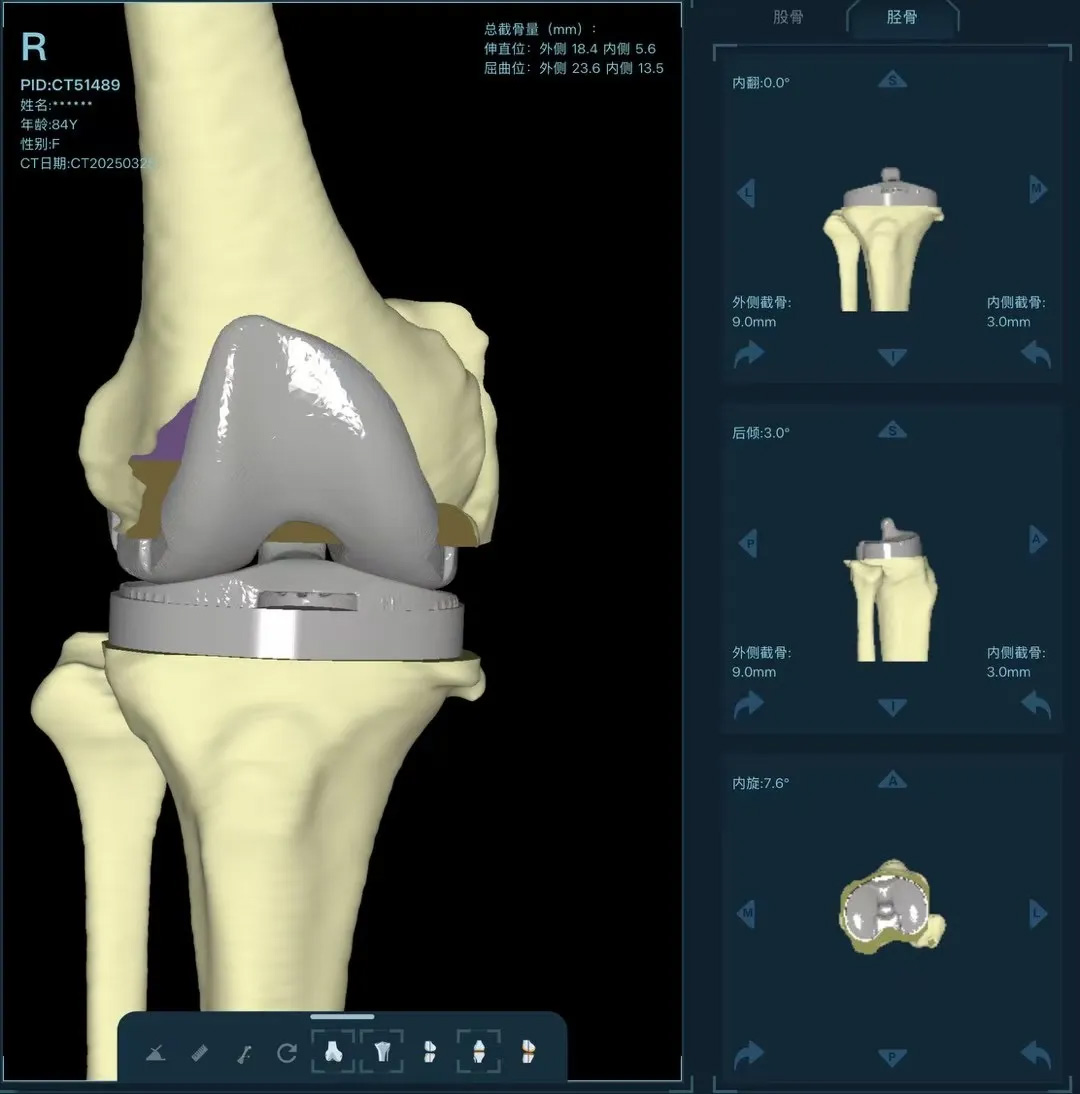

在家人幾乎放棄希望時(shí),AI三維規(guī)劃技術(shù)為這場"關(guān)節(jié)保衛(wèi)戰(zhàn)"帶來轉(zhuǎn)機(jī)。

術(shù)前:AI通過CT掃描生成毫米級膝關(guān)節(jié)三維模型,為假體安裝設(shè)計(jì)出誤差小于1毫米的精準(zhǔn)方案 術(shù)中:智能導(dǎo)航系統(tǒng)如同"透視眼",引導(dǎo)醫(yī)生避開密集的神經(jīng)血管網(wǎng),截骨更精準(zhǔn),出血僅100ml 術(shù)后:當(dāng)天鄭阿婆即開始抬腿的康復(fù)訓(xùn)練,24小時(shí)內(nèi)扶助行器下地行走,三天后已能在病房走廊獨(dú)立行走,完成洗漱用餐 兩周后健步出院時(shí),女兒含淚感慨“之前擔(dān)心她年紀(jì)大扛不住手術(shù),沒想到恢復(fù)這么快!現(xiàn)在每天散步比我還精神。知道技術(shù)這么先進(jìn),真該早點(diǎn)來!”

"這就像給傳統(tǒng)手術(shù)裝上了自動(dòng)駕駛系統(tǒng)。"主刀醫(yī)生羅軍副院長用生動(dòng)比喻解析技術(shù)突破。AI不僅實(shí)現(xiàn)假體“量身定制”,使用壽命可達(dá)20年以上,更通過三維路徑規(guī)劃將康復(fù)周期壓縮,實(shí)現(xiàn)術(shù)后24小時(shí)下地,2周回歸正常生活。同時(shí),AI會(huì)避開重要組織,具有出血少、感染風(fēng)險(xiǎn)低的特點(diǎn)。專家特別提醒,當(dāng)出現(xiàn)夜間持續(xù)性關(guān)節(jié)疼痛、步行能力低于10分鐘或關(guān)節(jié)畸形時(shí),應(yīng)及時(shí)就醫(yī)評估,"別等到關(guān)節(jié)'報(bào)廢'才手術(shù)"。